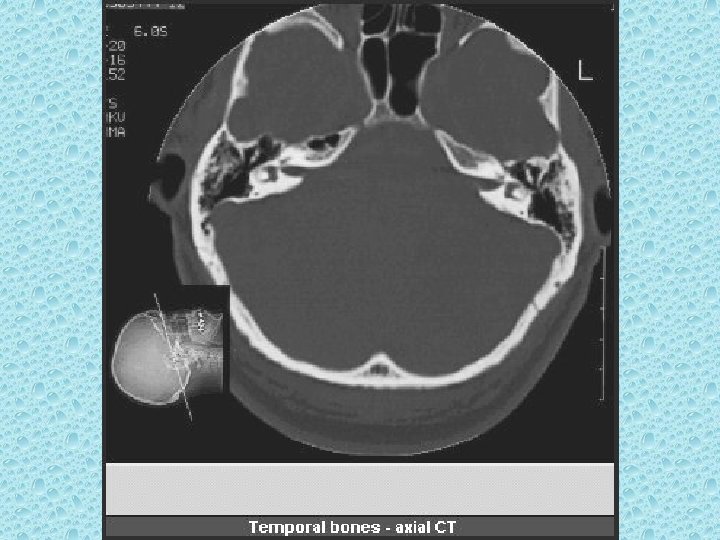

TEMPORAL KEMİK • • • Mastoid Petröz Skuamöz Stiloid proçes Zigomatik proçes

TEMPORAL KEMİKTE BULUNAN YAPILAR • • Kulak kepçesi Dış kulak yolu Timpanik zar Orta kulak ve kemikçikler: Malleus, inkus, stapes • İç kulak yolu ve yapıları: Kohlea, vestibül ve semisirküler kanallar